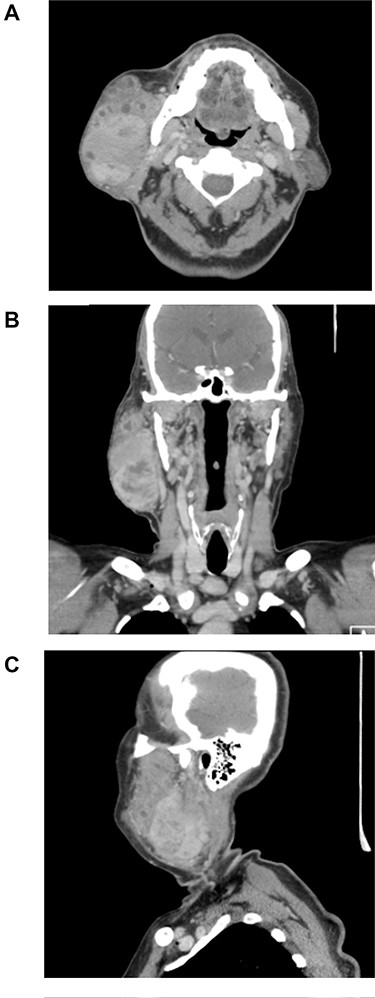

Contrast-enhanced CT head and neck demonstrated a huge, irregular, heterogeneously enhancing and solid cystic lesion, which was seen arising from the superficial lobe of the right parotid gland (Fig. 4). The lesion is collectively measuring 10 × 8.4 × 4.6 cm. There were multiple, solid enhancing nodules abutting the main lesion. There was significant surrounding fat stranding with thickening of the overlying skin.

Head and neck CT on the axial (A) coronal (B) and sagittal (C) planes.